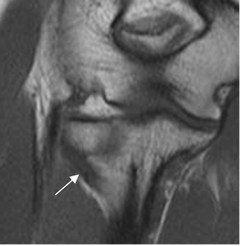

Fig 8. Lesión osteocondral

A: Rx AP. Osteopenia difusa por artritis reumatoidea, con disminución de los espacios articulares.

B: RM coronal en T1 y C: RM coronal en STIR. Lesión osteocondral del epicóndilo lateral, con erosión y alteración de la señal.